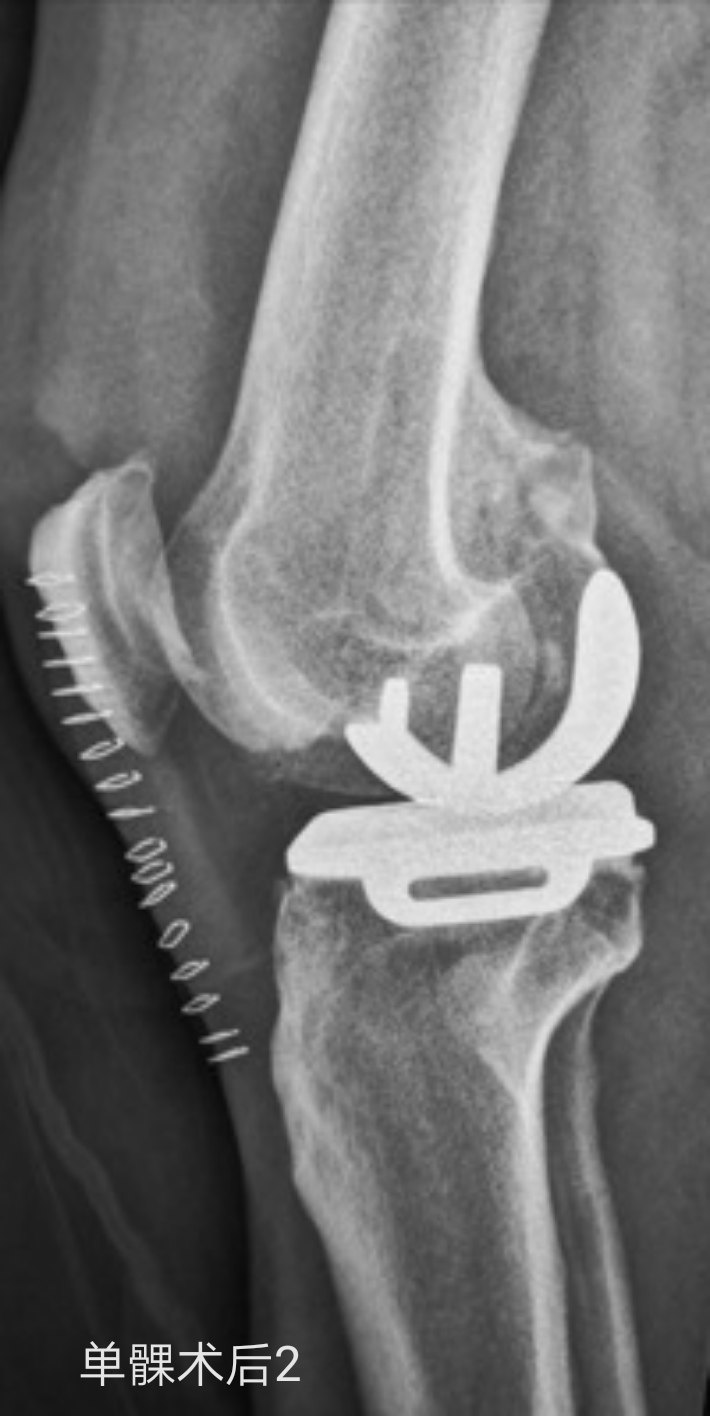

目前关节外科大夫所说的“保膝”手术,主要是指高位胫骨截骨术(HTO)和人工单髁表面置换术(UKA)两种,二者的共通点是在缓解疼痛症状的同时可以最大程度的保有您自身“原装”的膝关节骨质,不同的是前者HTO往往适用于年纪轻些的患者,而后者UKA往往适用于年纪稍大些的患者。当然,这只是非常笼统的说法,具体适合哪一种手术还是需要经过关节外科大夫的详细检查评估才能确定的。

下面就有两种手术的照片,请大家感受了解一下。如果您还有什么疑问,请您毫不犹豫的咨询熊奡大夫吧!